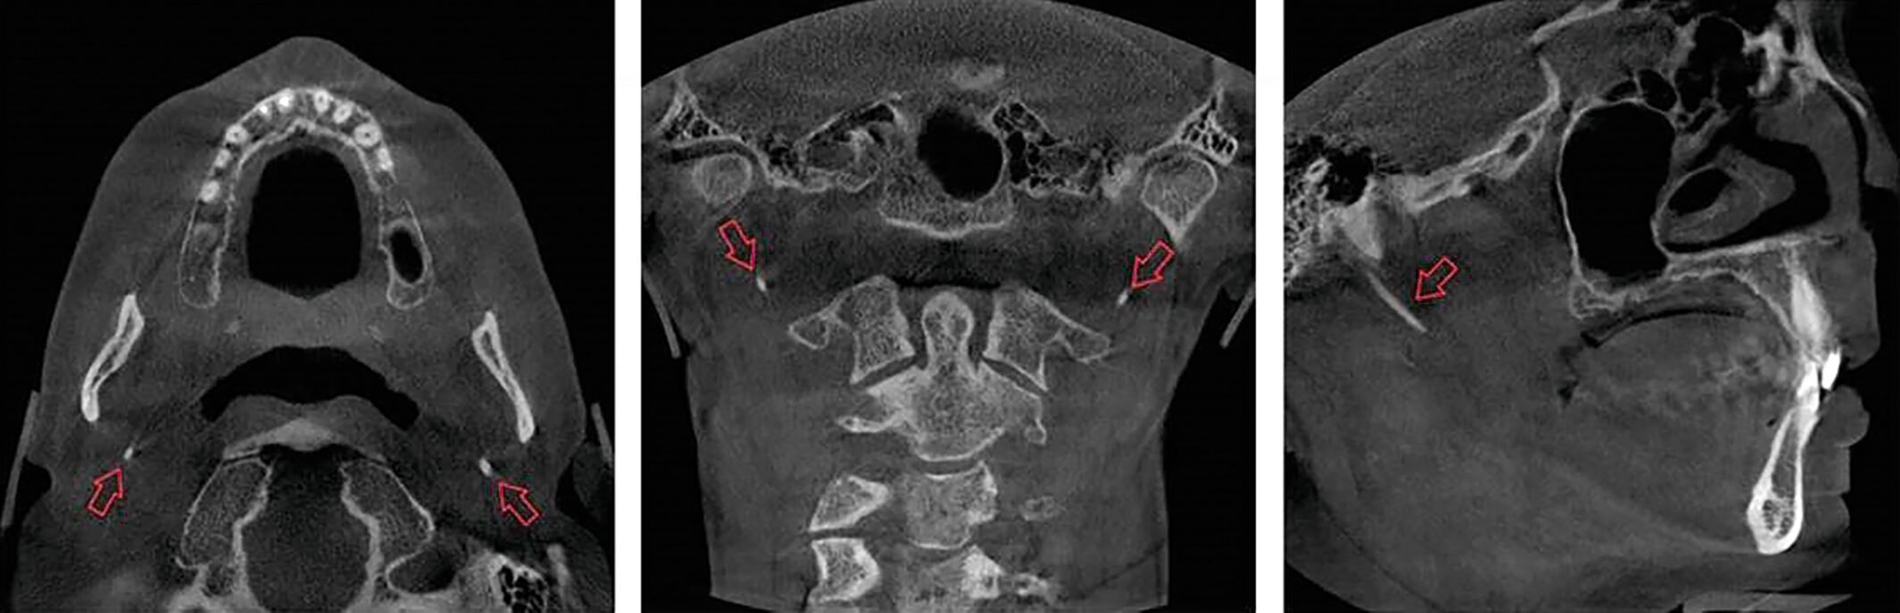

Die bildgebende Untersuchung mittels Orthopantomografie (Abbildung 1) und nachfolgender digitaler Volumentomografie (Abbildung 2) ergab eine Verlängerung des Processus styloideus beidseits, die auch im Rahmen einer dreidimensionalen Rekonstruktion dargestellt werden konnte (Abbildung 3). In Zusammenschau mit der beschriebenen Beschwerdesymptomatik wurde die Diagnose eines Eagle-Syndroms gestellt.

Die Diagnostik beruht auf einer klinischen Symptomatik, einem intraoralen und/oder extraoralen Tastbefund und einer Bildgebung [Piagkou et al., 2009]. Im Hinblick auf die Bildgebung gilt die dreidimensionale Bildgebung mittels Computertomografie als Goldstandard, wobei jene aber auch durch eine digitale Volumentomografie ersetzt werden kann [Oztunç et al., 2014; Badhey et al., 2017].

Ausschlaggebend für die Diagnose gilt in der Bildgebung eine Länge des Processus styloideus von über 25 mm und/oder eine ebenso lange Verkalkung des Ligamentum stylohyoideum [Searle und Searle, 2021]. Die Differenzialdiagnosen sind zahlreich, unter anderem Migräne, Clusterkopfschmerz, atypischer Gesichtsschmerz, Craniomandibuläre Dysfunktion, Trigeminusneuralgie, Mastitis, Tonsillitis und Otitis [Montalbetti et al., 1995; Piagkou et al., 2009].